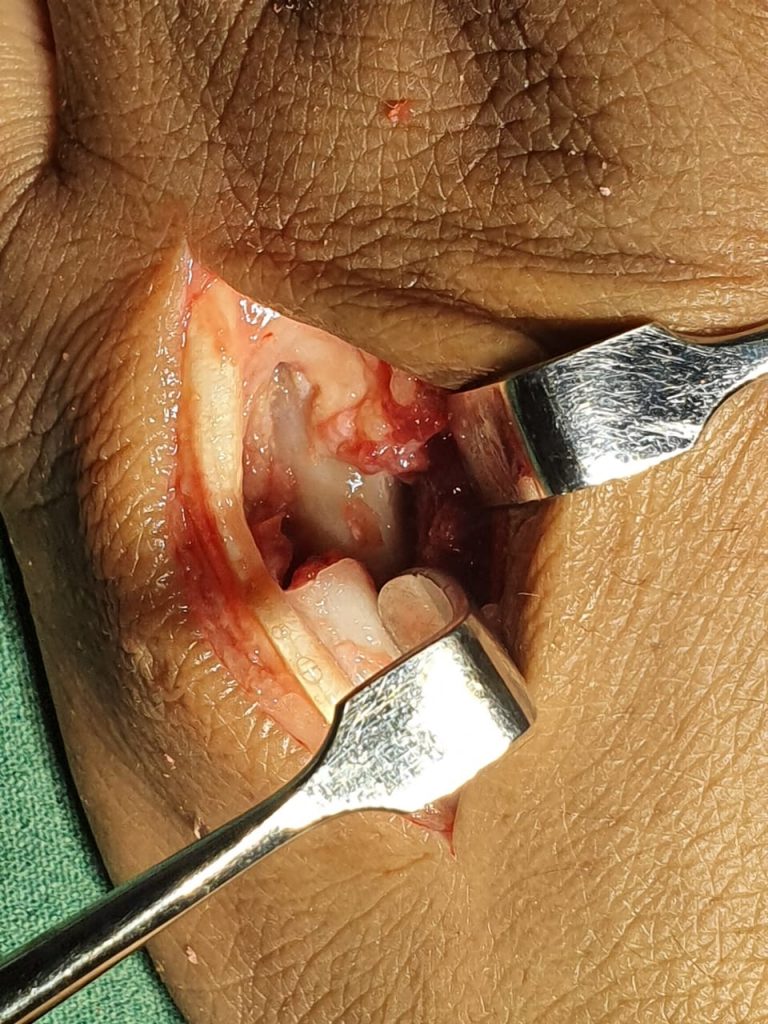

Cirugía de mano